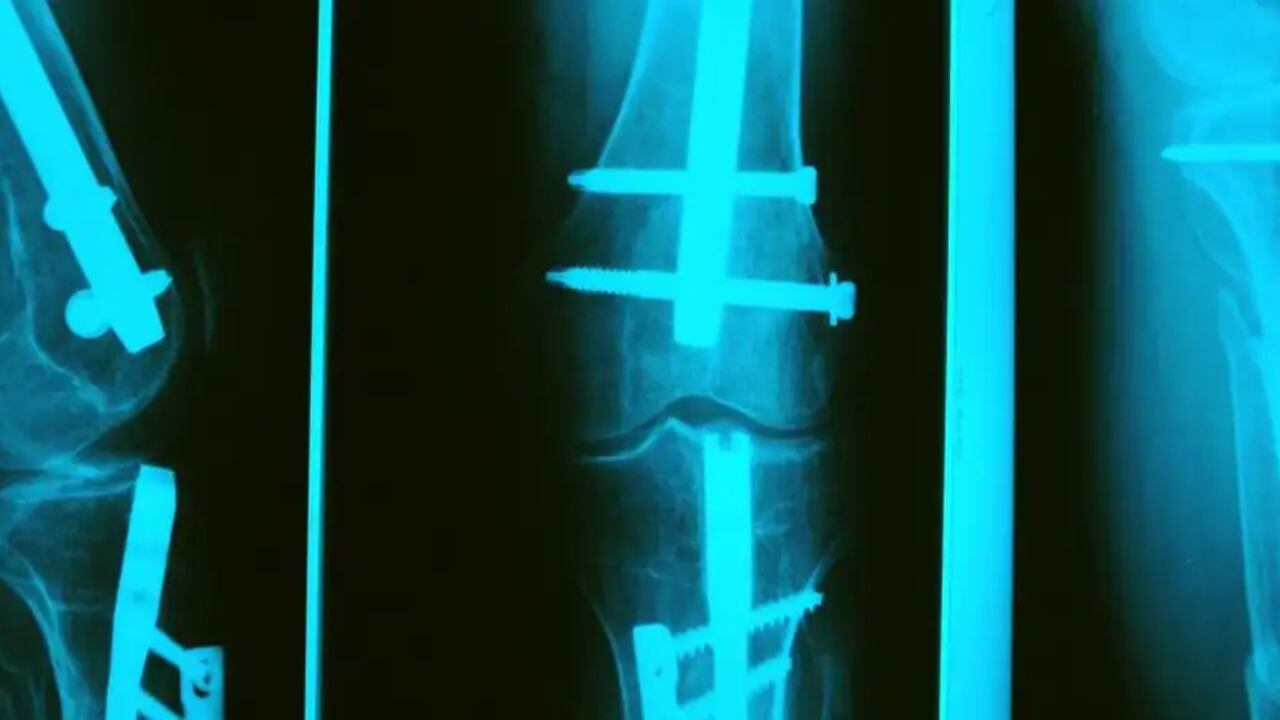

Los alemanes se demoraron doce años en crear un perno de magnesio. ¿Para qué? Cuando alguien se rompe la pierna, se fractura un hueso o lo que sea, le ponen un perno de magnesio para que se suelde más rápido. Y, cuando ya se soldó, sacan la radiografía y no hay perno.

Esto significa que los pernos de magnesio son altamente biocompatibles, es decir bien tolerados por el cuerpo humano y no provocan reacciones adversas significativas. A diferencia de los implantes metálicos tradicionales (como los de acero inoxidable o titanio), los pernos de magnesio son biodegradables. Se descomponen gradualmente en el cuerpo y se absorben de manera segura, eliminando la necesidad de una segunda cirugía para retirarlos.

Su capacidad para promover la curación ósea, eliminar la necesidad de cirugías y reducir el riesgo de complicaciones los hace una opción prometedora para diversas aplicaciones clínicas.